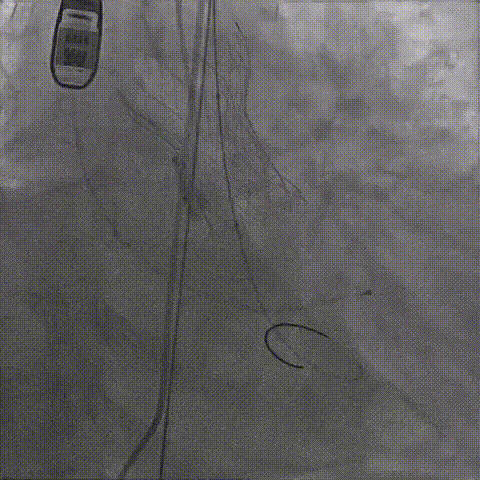

根部造影;直头导丝顺利跨瓣

23mm球囊预扩,冠脉显影正常;输送器顺利过弓

初次释放,无冠窦畸形猪尾难以到达窦底,定位带来挑战;释放至工作位,瓣膜(AV29)位置偏低